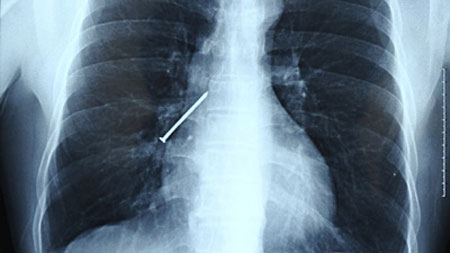

Khi đang ngậm đinh ở răng để làm việc, Li Xiangyang (48 tuổi) ở thành phố Hoàng Thạch, tỉnh Hồ Bắc bất ngờ ho và nuốt nó vào người. Ông nhanh chóng được đưa tới một bệnh viện gần trường Đại học Vũ Hán để cấp cứu. Tại đây, qua chụp X-quang, các bác sĩ phát hiện chiếc đinh nằm ở phổi phải.

Chiếc đinh dài 15cm nằm trong phổi của Li.

Nhận thấy cần phải lấy nó ngay ra khỏi cơ thể, giáo sư Hu Ke luồn một ống soi phế quản xuống cổ họng để lấy chiếc đinh ra. Tuy nhiên, khi ông Hu sắp lấy được chiếc đinh ra khỏi miệng, thì Li lại ho và khiến chiếc đinh rơi xuống cổ họng.

Lần này, chiếc đinh lại nằm ở phổi trái và giáo sư Hu lại tiếp tục lấy nó ra. Nhưng cũng như lần trước, Li vô tình nuốt chiếc đinh và nó lại biến mất khi sắp được lấy ra.

Loay hoay mãi mà không tìm thấy chiếc đinh nằm ở phổi, các bác sĩ sau đó phát hiện nó đã trôi xuống dạ dày của bệnh nhân. Cuối cùng, bác sĩ dùng ống soi dạ dày để lấy được nó ra khỏi bụng của ông Li.